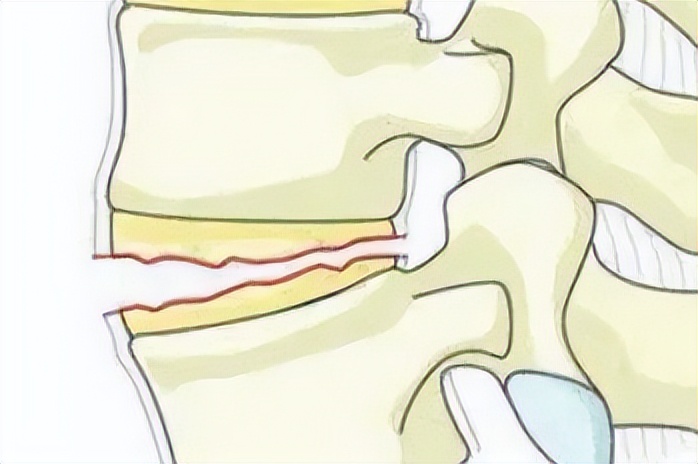

脊柱骨折是脊柱创伤中比较常见的损伤,其中又以胸腰段椎体骨折最为常见,脊柱骨折后出现脊髓压迫等神经症状应该行急诊手术以尽早解除脊髓压迫。

对于无脊髓神经症状患者则根据症状、体征以及患者的全身情况综合制定治疗方案,择期手术治疗为首选治疗方式。

传统医学把脊柱骨折归为中医骨伤病范畴,外伤导致脊柱骨折,椎体局部骨断筋离,患处筋脉受损,血溢脉外,气血阻滞,不通则痛;早期多出现气滞血瘀的症状,继而兼有气虚血瘀症状。中医骨伤范畴中,三期辨证是逐渐发展推陈出来的,其中隋唐时期蔺道人开创中医骨伤科分期论治的先河。

清代医家将骨折愈合过程概括为“瘀去”“新生”“骨合”3个阶段,与现代医学研究中的骨折生理愈合阶段不谋而合,标志着中医骨伤科三期辨证最终形成,三期辨证体系主张早期治以活血化瘀、行气止痛。